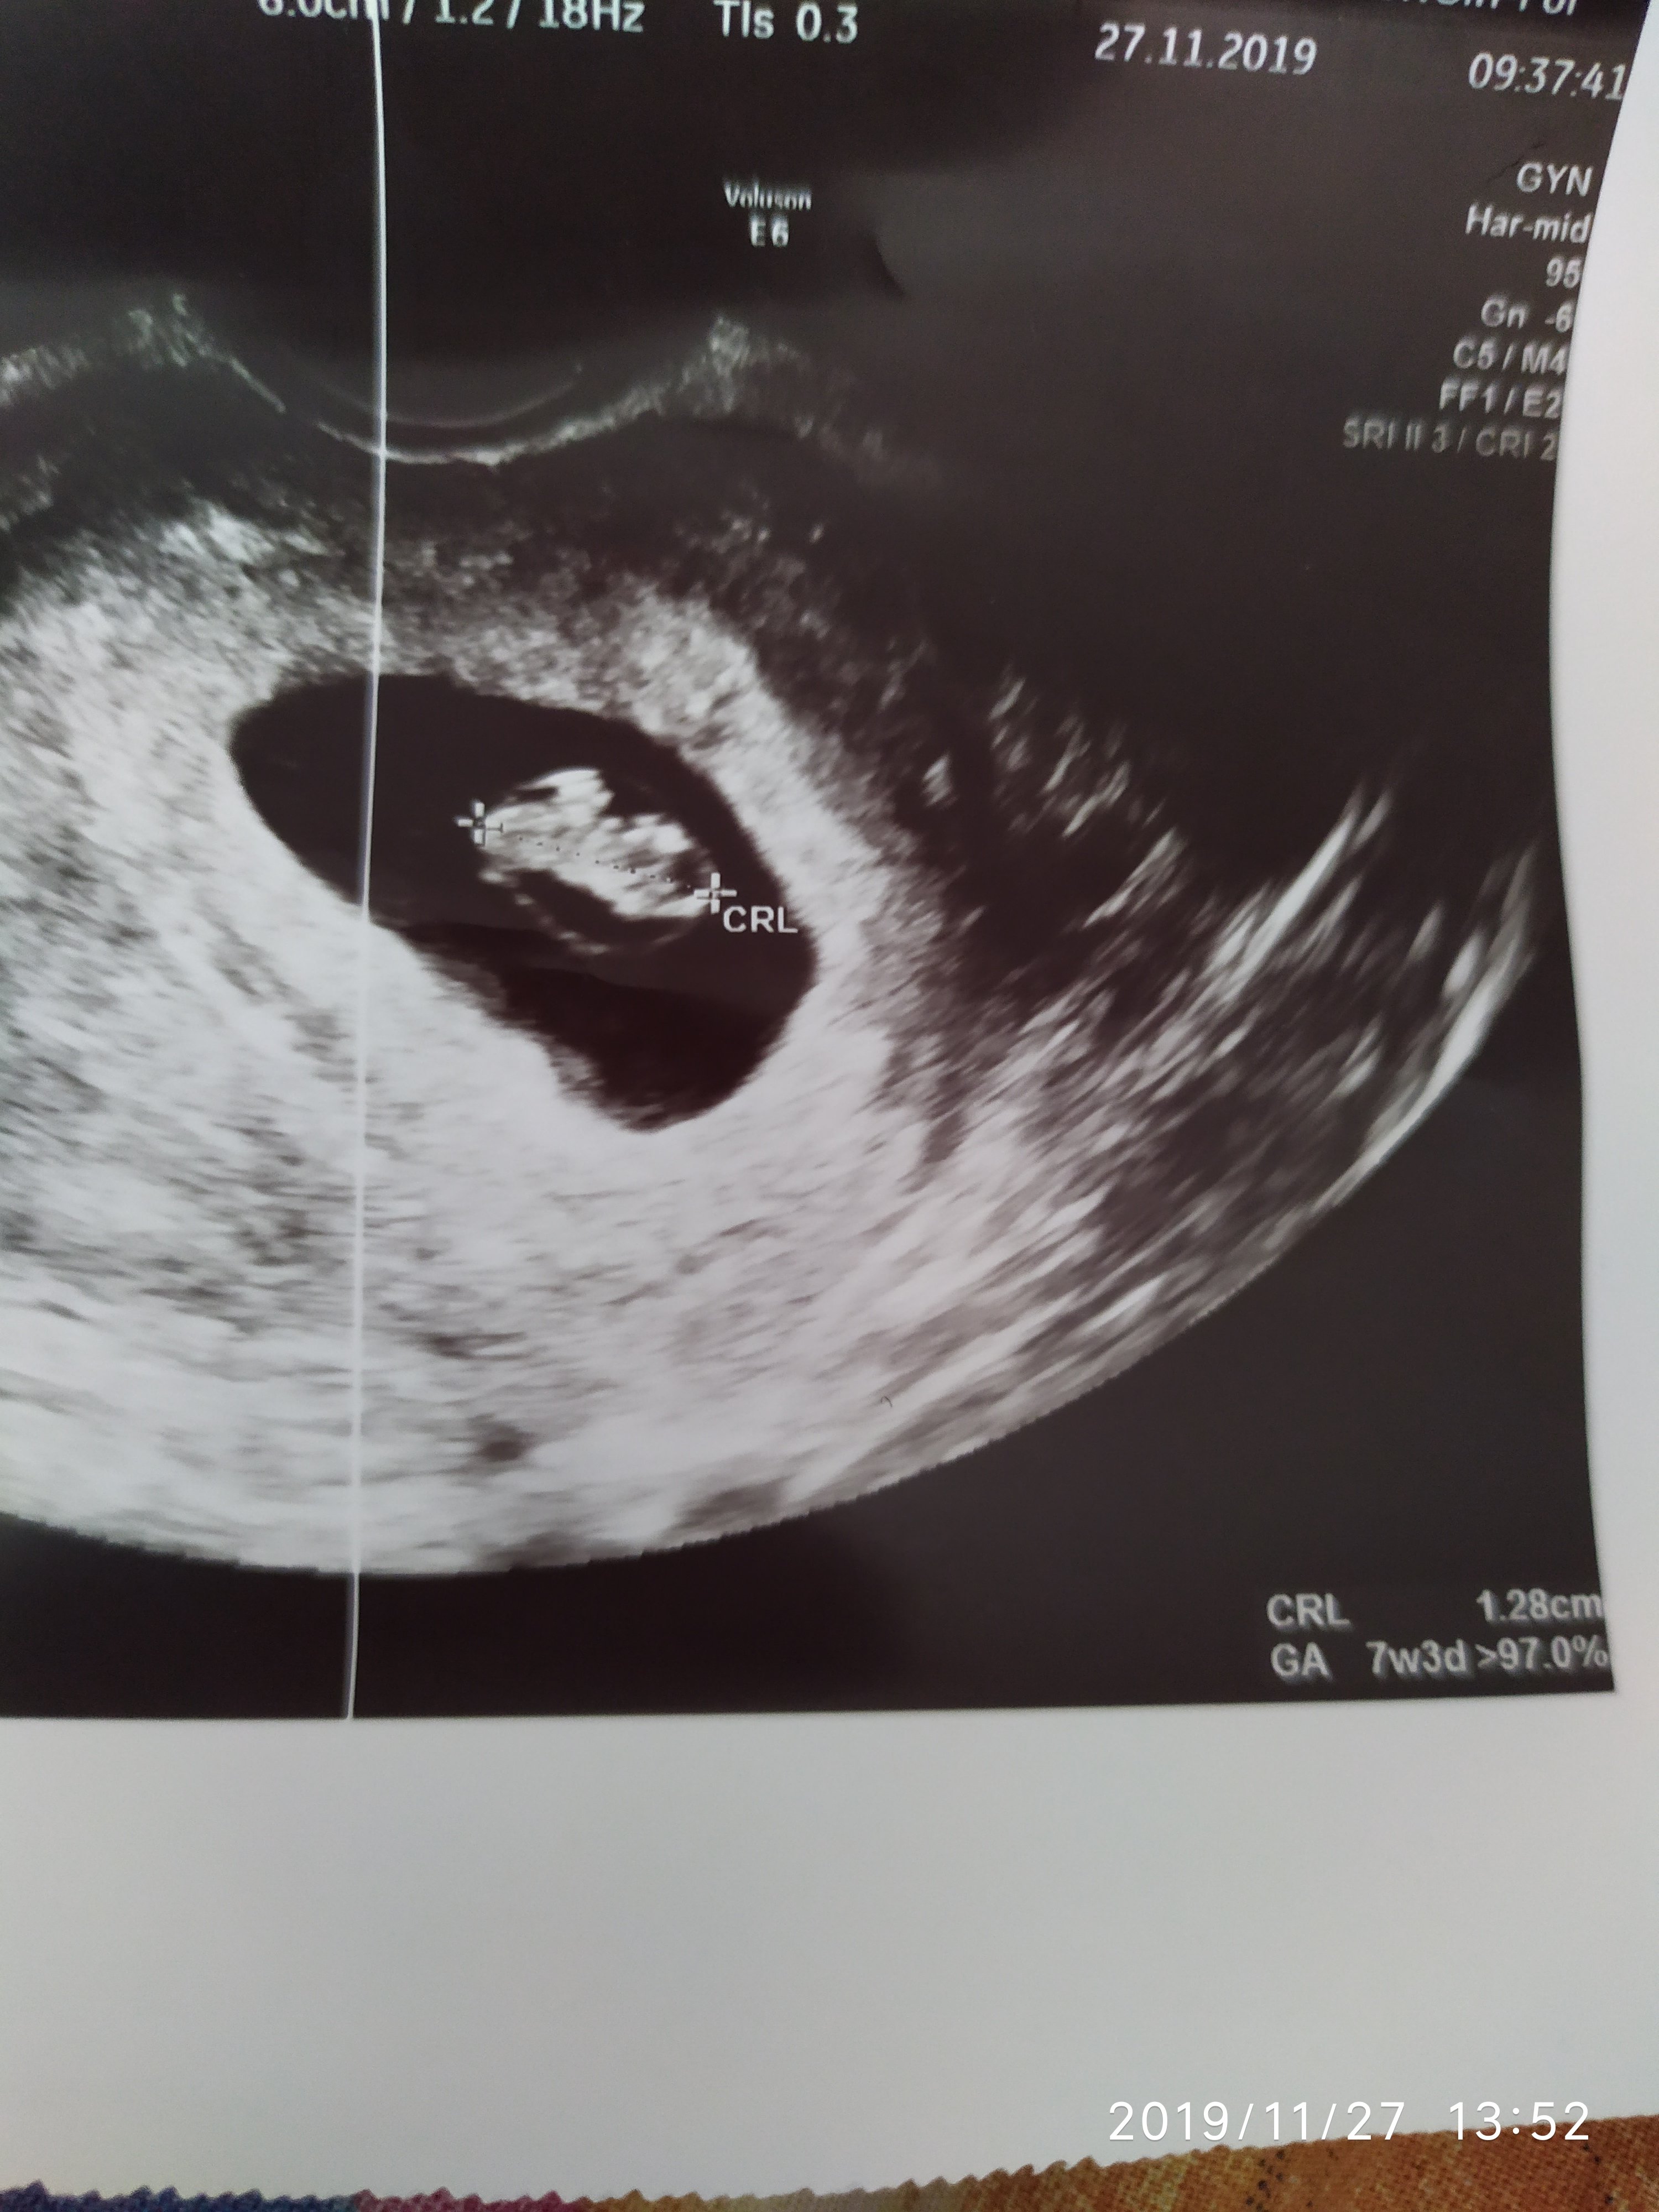

Dawno mnie tu u was nie było.Zagladam codziennie ale jakoś brakuje czasu na pisanie. Dzisiaj muszę się pochwalić maleńkim bijącym serduszkiem. Cudnie słuchało się tego po raz trzeci.

IMG_20191127_135257.jpg